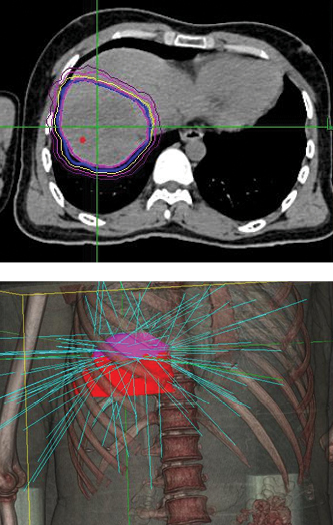

Phase 1 treatment covered the right lower lobe and hilar nodes, divided into two targets. The prescription was 48 Gy, delivered in four 12 Gy fractions for each of the two targets. Bilirubin fluctuations were noted during the course of therapy, but gradually returned to normal after treatment. One month after radiotherapy, a CT scan showed tumor shrinkage. The left lobe had sufficiently enlarged in compensation, so the second stage of treatment was initiated.

Phase 2 treatment covered the right upper lobe, divided into two targets: The prescription was 39 Gy, delivered in three 13 Gy fractions for each of the two targets.

“The patient lived more than two years with good quality of life after initial diagnosis, when life expectancy would have been one month without CyberKnife treatment.”